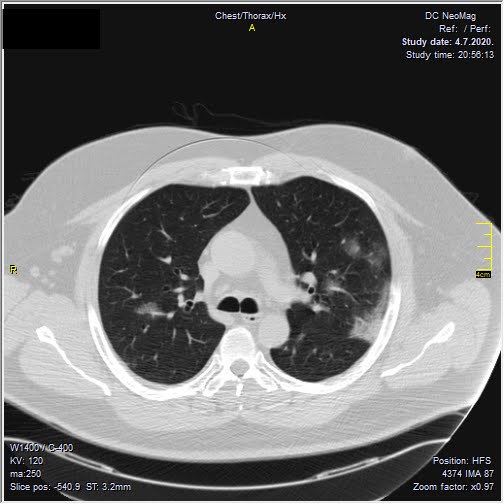

Foto: Aleksandar Ivković Foto: Aleksandar Ivković Foto: Aleksandar Ivković Zastrašujući snimci skenera pluća od 1. do 15. dana kovida autor: Božica Luković Zdravlje 26. nov. 2020. 12:33 > 26. nov. 2020. 13:35 0 Podeli vest: Kovid 19 je nepredvidiva bolest koja u razmaku od par dana može iz blage da preraste u opasnu po život. Kako koronvirus utiče na pluća iz dana u dan, pokazao je na snimcima CT skenera srpski radiolog Aleksandar Ivković. Podeli vest: Oglas Lekar iz Niša na svom blogu "Ljudi i ostale laži" redovno piše o svim važnim temama u vezi sa koronavirusom, a sada je odlučio da prikaže CT skenere pluća osobe obolele od kovida 19.Objasio je šta lekari tačno prate kada su u pitanju snimci pluća, ali i kako se te stavke menjaju kako bolest napreduje.Njegovu objavu prenosimo u celosti."Vraćam se na svoju usku struku (da ne bude da se mešam u tuđu). Kompjuterizovana tomografija, skener ili CT je metoda pregleda koja je superiorna kod zapaljenskih bolesti pluća. Kod kovida 19 se pokazala kao nezamenjiva u diferencijaciji u odnosu na ostale bolesti. Tačnost nalaza na plućima je visoka. Šta mi to možemo videti i kako tumačimo? Stvari koje pratimo su:- Ground glass konsolidacije (GGO).To su one bele "mrlje" na snimcima koje su karakteristične za ovu bolest. Nazivaju se "ground glass" svuda. Izgledaju kao da se taj deo pluća gleda kroz mlečno staklo, kao neka vrsta mikromozaika. Foto: Aleksandar Ivković | Foto: Aleksandar Ivković - Crazy paving.To su linearna zadebljanja koja se nekada vide u ground glass konsolidacijama. Ona nastaju kasnije, ne javljaju se pre GGO. Neko ih opisuje kao da pijani majstori slažu pločice. Na slikama se to vidi kao nepravilna zadebljanja unutar GGO, složena bez ikakvog reda. Foto: Aleksandar Ivković | Foto: Aleksandar Ivković - Vaskularne dilatacije. Dolazi do zapaljenskog procesa krvnih sudova i/ili do zastoja tako da su nam na snimcima krvni sudovi "deblji". Foto: Aleksandar Ivković | Foto: Aleksandar Ivković - Trakcione bronhiektazije. To su proširenja vazdušnog prostora (ali ne onog koji učestvuje u disanju) koja nastaju kada stradaju alveole i proširuje se prostor između njih. Foto: Aleksandar Ivković | Foto: Aleksandar Ivković - Arhitektonske distorzije. Pojava traka blizu pleure koje nastaju propadanja plućnog tkiva i nastanka fibroznog. Foto: Aleksandar Ivković | Foto: Aleksandar Ivković Svaki od ovih znaka se može javiti i kod drugih bolesti ali svi zajedno su specifični za kovid-19Da bi objasnili stanje koristimo Severity Score. On služi za procenu ozbiljnosti bolesti. Pluća se sastoje od pet lobusa. Procenjuje se svaki pojedinačno ocenama od 0 do 5. To znači da se skor kreće od 0 do 25.0 - znači da nema GGO konsolidacija1- znači da je manje od 5% tog lobusa zahvaćeno2 - znači da je zahvaćeno od 5 do 25% tog lobusa3 - znači da je zahvaćeno 26 do 50% tog lobusa4 - znači da je zahvaćeno 51 do 75% tog lobusa5 - znači da je zahvaćeno više od 75% tog lobusa Na CT razlikujemo 4 faze (najčešće ali nije decidirano tako) Rana faza (0 do 4. dan) - pojedinačne GGO, neka crazy paving, nizak skor Foto: Aleksandar Ivković | Foto: Aleksandar Ivković Progresivna faza (5. do 8. dan) - povećanje broja GGO i crazy paving Foto: Aleksandar Ivković | Foto: Aleksandar Ivković Pik faza (10. do 13. dan) - javljaju se konsolidacije pluća, to znači da veliki delovi pluća izgledaju kao velike bele površine a označavaju delove pluća koji su masa koja koja je u celini zahvaćena zapaljenskim procesom. Foto: Aleksandar Ivković | Foto: Aleksandar Ivković Faza rezolucije (posle 14. dana) - vraćanje delova pluća u normalu ili smrt Foto: Aleksandar Ivković | Foto: Aleksandar Ivković Iskustveno smo došli do skora 15 koji predstavlja neku granicu između verovatno dobrog i verovatno lošeg ishoda. Samo tumačenje zavisi od faze bolesti. Naš nalaz je samo deo procene i ne menja laboratorijske i pulmološke, kao ni ostale. Svaki nalaz zajedno daje ukupnu sliku bolesti. Foto: Aleksandar Ivković | Foto: Aleksandar Ivković Nalaz je u88% slučajeva sa obe strane,88% ground glass,80% posteriorno,79% multilobularno,76% periferno i30% konsolidacijeTo je posao radiologa, to je moj posao. Sasvim sigurno je da bez ovih slika lečenje ne bi bilo lako. Pacijente delimo na lake - one koji nemaju tegobe, teške - one koji imaju zahvaćeno do 50% pluća i kritične a to su oni kod kojih je više od 50% zahvaćeno", piše dr Ivković.***Bonus video:https://www.youtube.com/watch?v=fYeYlhqeD5cPratite nas i na društvenim mrežama:FacebookTwitterInstagram Revolucija iz Niša: Test na koronu koji predviđa tok bolesti Zdravlje 0 Tekst naučnika koji ruši sve zavere o koroni - i daje nadu Zdravlje 0 72 sata pakla od kad su me zabolela pluća u kovid Srbiji Zdravlje 0 aleksandar ivković ct skener koronavirus kovid-19 pluća Pratite nas na društvenim mrežama: Koje je tvoje mišljenje o ovoj temi? Učestvuj u diskusiji ili pročitaj komentare Budite prvi koji će ostaviti komentar Pošalji komentar Pročitaj komentare (0)